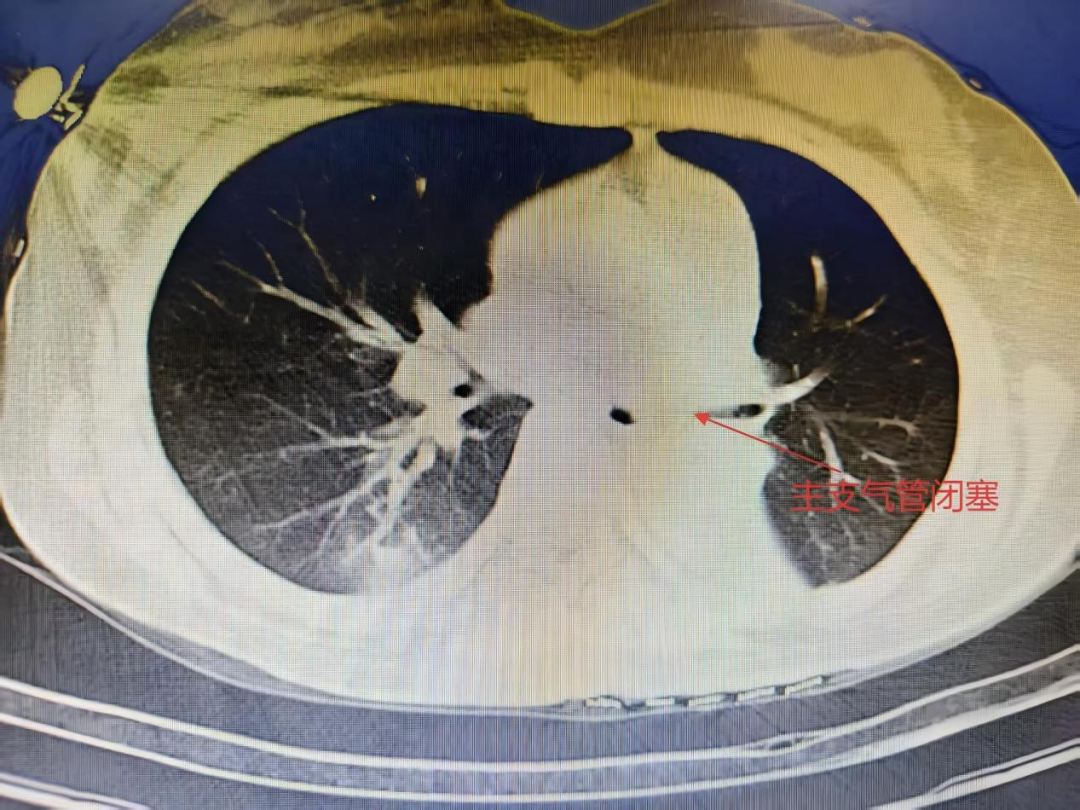

抵达石大一附院急诊医学中心时,院内抢救团队早已严阵以待。持续心肺复苏、呼吸机辅助通气……监护仪的每一次波动都牵动着所有人的心。终于,在多学科医护人员的共同努力下,患者恢复了自主心率。随后,以“呼吸心跳骤停、呼吸衰竭、吸入性肺炎”等诊断转入EICU,接受进一步救治。 入院时,患者仍处于深昏迷状态。头颅CT提示脑水肿,胸部CT显示双肺背段实变、支气管闭塞——误吸导致的严重气道阻塞和肺部感染,成为救治过程中必须闯过的关键难关。 随后,EICU团队迅速联系呼吸与危重症科刘冬主任医师,急诊行电子支气管镜检查。镜下可见隆突及各叶段支气管黏膜充血明显,右肺中下叶及左肺下叶被粘稠痰液堵塞,常规吸引难以清除。在机械通气、抗感染、脑保护及器官功能支持的基础上,医疗团队对双肺多个肺段实施支气管镜灌洗治疗。随着粘稠痰液被逐步清除,气道恢复通畅,为呼吸功能改善创造了重要条件。 经过一周的全力救治,患者意识逐渐清醒,自主心率与呼吸平稳恢复,生命体征趋于稳定。复查胸部CT显示,双肺渗出性病变较入院时明显吸收,气道通畅,各项指标显著好转。4天后,患者顺利脱机并拔除气管插管,转出内科EICU。 此次成功救治,是石大一附院“以患者为中心”理念的生动实践。从院前急救的果断处置,到院内生命支持的精准施策,再到后期治疗的细致入微,每一个环节都凝聚着急诊医学中心团队的专业与担当。医护人员时刻关注患者的点滴变化,及时调整治疗与护理方案,用医学的严谨和人性的温度,陪伴患者走过最艰难的时刻。正如一位参与救治的医生所说:“我们不只是抢救一个生命,更是守护一个家庭的希望。” 生命在医患同心的呵护下重新绽放。石大一附院急诊医学中心将继续秉持“救死扶伤、大爱无疆”的职业精神,不断提升急危重症救治能力,为守护边疆各族人民的生命健康筑牢坚实防线。 供稿|急诊医学中心 张天 秦练 编辑|朱思佳 编审|于 磊 王晓民 权江宏 杨 涛